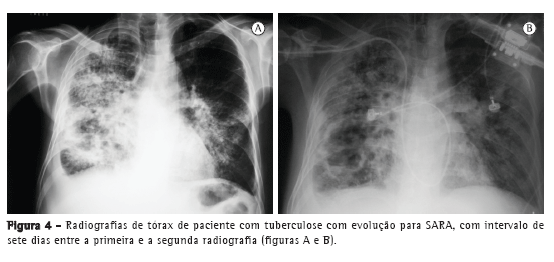

Com relação aos achados radiológicos, infiltrados reticulares e consolidação são os padrões mais frequentes,(5,6,10,15,17) sendo que cavitação pode estar presente em 27-50% dos casos.(6,10,16) As Figuras 1 a 4 mostram alguns dos principais padrões radiológicos nesse contexto.

Os pacientes com tuberculose e necessidade de cuidados intensivos podem evoluir para síndrome da angústia respiratória aguda (SARA). A incidência descrita de SARA é variável: 12,1%,(10) 13,4%,(15) 28,1%(5) e, em alguns estudos, até mais de 60%.(6,16) Em uma série de casos com 15 pacientes hospitalizados com tuberculose e insuficiência respiratória, apesar das características clínicas e radiológicas compatíveis com SARA, os achados histopatológicos foram compatíveis com broncopneumonia tuberculosa, sem evidência de SARA.(7) Em um estudo no Brasil, as alterações histopatológicas pulmonares encontradas em autopsias de pacientes que evoluíram a óbito por insuficiência respiratória aguda foram revisadas, e o principal padrão associado com tuberculose foi o dano alveolar difuso.(11)

O tempo entre o início dos sintomas e o início do tratamento antituberculose descrito nos estudos foi maior do que 30 dias em 28,8-34,0% dos casos.(6,17) O tempo entre a admissão e o início da terapêutica adequada foi avaliado em apenas um estudo, sendo relatada uma média de 4,3 dias. Naquele estudo retrospectivo, o tempo entre a admissão e o início do tratamento foi menor nos pacientes com tuberculose miliar do que naqueles com pneumonia tuberculosa (2,8 ± 2,5 dias vs. 5,0 ± 7,0 dias; p = 0,048).(16) Pode haver atraso no diagnóstico e, consequentemente, no começo do tratamento pela difícil diferenciação radiológica entre pneumonia tuberculosa e pneumonia bacteriana grave. Considerando essa dificuldade na distinção entre as duas patologias, um estudo avaliou as diferenças nas características clínicas e radiológicas de pacientes com pneumonia grave com e sem tuberculose internados em UTIs. A história de sintomas com duração maior do que duas semanas e a presença de micronódulos ou de padrão cavitário na radiografia de tórax foram significativamente associados com tuberculose pulmonar ativa.(20) Adicionalmente, o padrão miliar na radiografia de tórax também pode ser erroneamente interpretado como insuficiência cardíaca congestiva.(18)